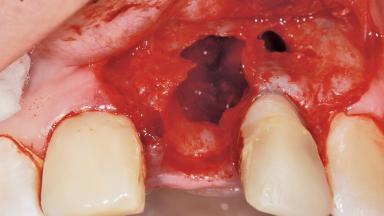

Late Placement of an Implant in a Maxillary Left Central Incisor Site

A 36-year-old female patient was referred for the replacement of the upper left central incisor (tooth 21), which had fractured. Although the tooth had been asymptomatic for many years, the crown began to loosen, at which time she presented to her dentist for an assessment. Teeth 21 and 22 had both been endodontically treated many years previously. She was a healthy individual and a non-smoker.

On examination, the patient had a low lip line and only displayed the coronal half of the anterior teeth when smiling.

The crown of tooth 21 was splinted to the adjacent teeth with composite resin, and the gingiva was inflamed.

Bone Volume Deficient horizontally, requiring prior grafting